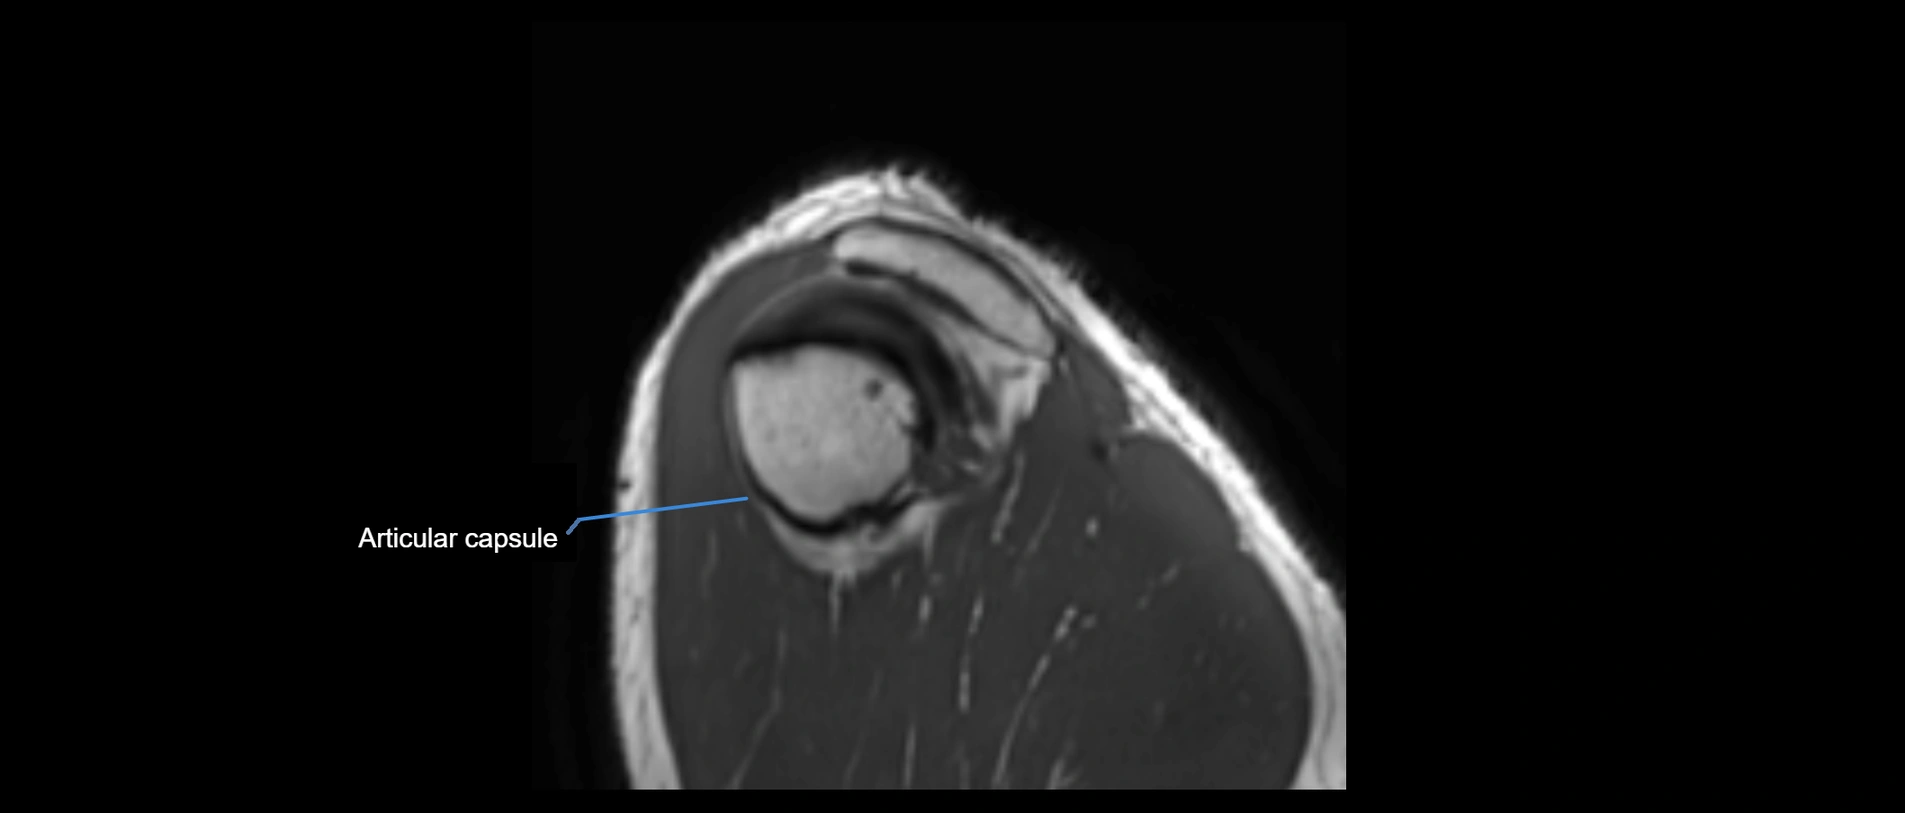

MRI images

image